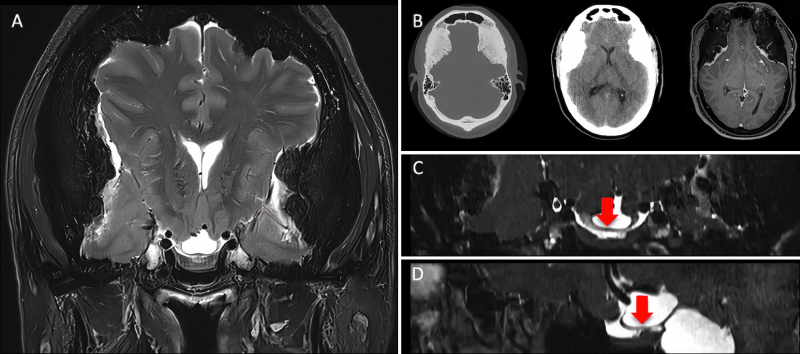

Observations: The authors present the case of a 52-year-old patient with progressive optic neuropathy due to bilateral hyperostotic frontotemporal MEP. Long-standing intracranial hypertension caused by mass effect had led to formation of a suprachiasmatic cyst deflecting the optic chiasm. The authors aimed to lower the intracranial pressure indirectly by performing a targeted, right-sided craniectomy with tumor removal and mesh cranioplasty. Postoperatively, reconstitution of brain anatomy and stabilization of the optic neuropathy were observed.